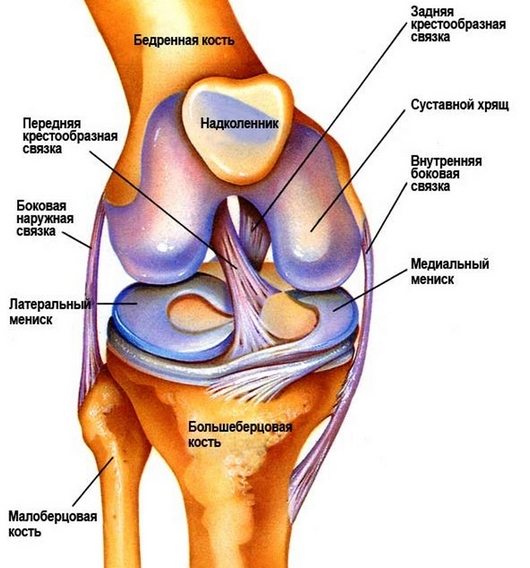

Коленный сустав – самый задействованный в организме, постоянно подвергается нагрузкам. В сгибании колена участвует много мышц, при ослабевании работы которых происходит повышенная нагрузка на сустав и его оболочки. Дискомфорт и болевые ощущения в коленном суставе – это проявление обратимых или других процессов, которые выявит только специалист.

- Растяжения и разрывы связок суставной сумки колена.

- Травмы колена.

- Бурсит коленного сустава.

- Травматические повреждения мениска.

- Переломы костей и состояние после перелома прилегающих костей.

- Вывих и привычный подвывих в коленном суставе.